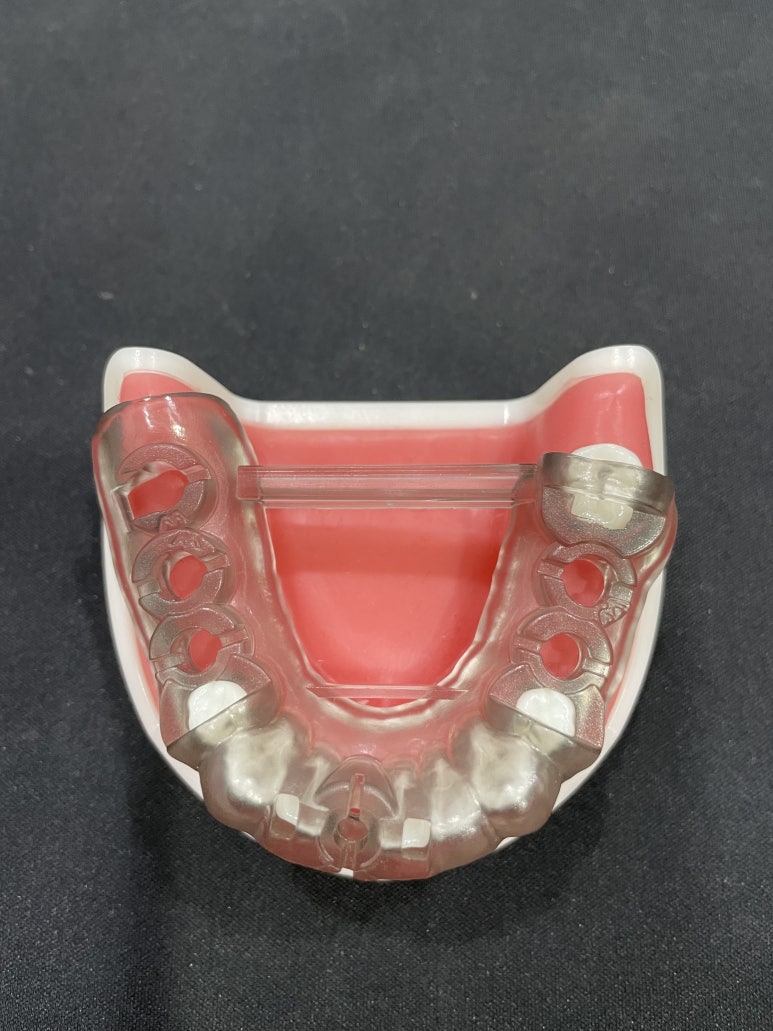

네비게이션 임플란트 수술을 위한 원가이드 샘플

환자분의 구강 및 골격의 구조 등을 면밀하게 파악해 환자분께 딱 맞는 가이드를 제작해야 하는데

이 제작비용이 추가되기 때문에 일반 임플란트보다 조금 더 비싼 것입니다.